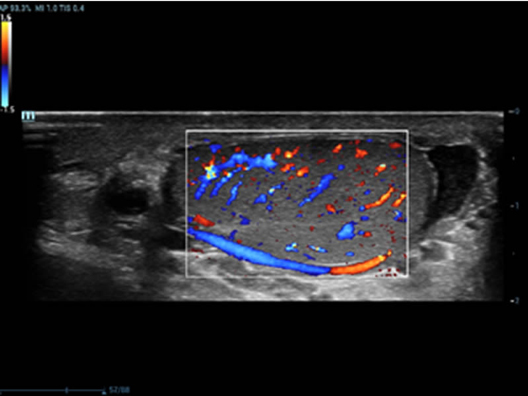

Oltre alla qualit├Ā delle immagini di livello eccellente, Resona 7 migliora anche le capacit├Ā di ricerca clinica il rivoluzionario V Flow per la valutazione emodinamica vascolare, e l'acquisizione piani pi├╣ intelligente dal set di dati 3D per la diagnosi del sistema nervoso centrale fetale. Combinando il pi├╣ intuitivo funzionamento multi-touch basato su gesti e tutte le caratteristiche cliniche essenziali, Resona 7 sta veramente portando nuove tendenze nellŌĆÖinnovazione dellŌĆÖecografia.